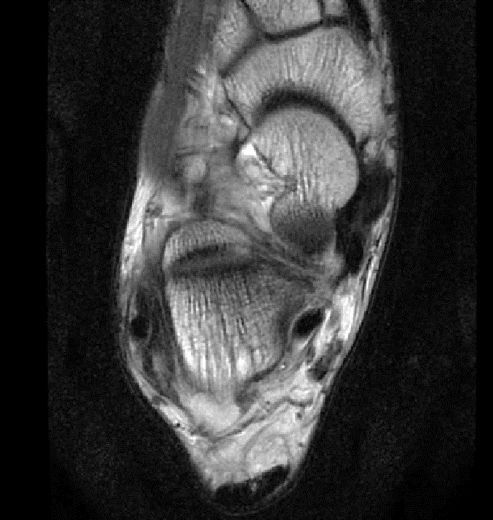

此片可以看到韧带结构消失,T2相高信号,整体韧带增粗,松弛,腓骨肌腱内侧,跟绯肌腱的形态完全消失,它的韧带也是松弛增粗的。所以考虑是踝关节距腓前韧带的损伤。